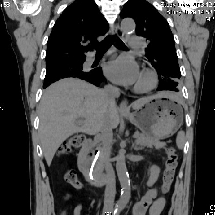

原来,老张8年前因胆总管狭窄腹痛,在其他医院行胆道支架置入,本来三个月后就要取出,老张出院后却将拔除支架的事忘得一干二净,最近又出现了胆管疾病的症状才来医院就诊。检查发现,老张胆管支架堵塞,胆管内多发结石,腹痛皆因于此。本来胆管结石可以通过经内镜逆行性胰胆管造影术(ERCP)微创解决,但老张的支架却牢牢嵌顿在胆管中了,若强行取出可能造成胆道出血。

▲支架深嵌在胆管里

因此,老张只能通过外科手术开刀取出支架,但因其胆管直径较细,手术难度较大,强行拔除支架可能出现肠瘘、出血、胆管狭窄等危险。而且还要在两个不同的科室完成两次手术,不仅仅增加痛苦,更增加住院时间和医疗总费用。

经过详细的多学科讨论后,邱福南主任医师团队最终决定为老张实行胆道镜、胃镜、腹腔镜(三镜)直视下胆总管切开术取出结石及支架,术中探查见支架近端包埋于胆管、远端嵌顿于肠管,难度重重。